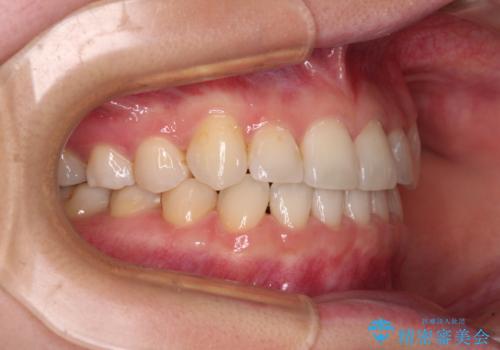

- 八重歯を気にして来院された患者様です。

口腔内の状況を確認したところ、左右ともに下顎第二大臼歯が欠損しており、咬み合うべき上顎の第二大臼歯が著しく挺出していました。

順調に後方移動することができ、わずか1年強で治療を終えることができました。

顎骨が小さいので第二大臼歯が欠損しても負担は少ないと思いますが、奥歯でもっとしっかりと咬みたいということであれば、インプラント補綴治療を4本分行うこととなります。